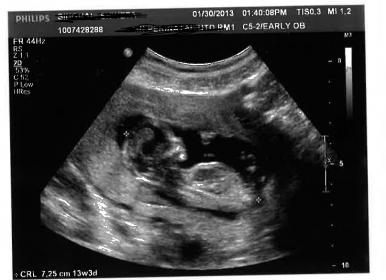

These were taken at 13w3D

Is there any nub? what about skull theory?

thanks Inky. So what is that white thing in the bottom? I thought that was nub.

Couple days for the gender scan... any final guesses ?? may be skull theory?